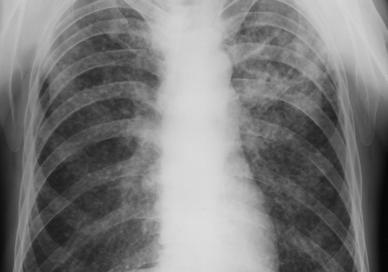

Fig. 14 – Pneumonie lobara superioara dreapta in rezolutie (opacitate sistematizata neomogena, de intensitate mica spre medie, delimitata inferior de mica scizura, ocupand LSD)